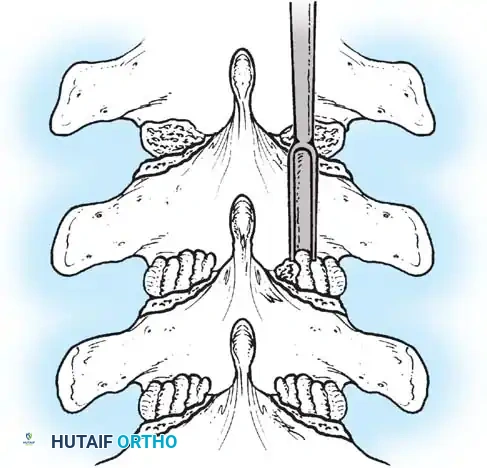

The Moe Technique (Lumbar Spine)

In the lumbar spine, the facet joints are oriented in a more sagittal plane, necessitating a modified approach.

Fig. 38-27: The Moe technique adapted for lumbar facet fusion, addressing the sagittal orientation of the joints.

- Utilize a small osteotome or a needle-nose rongeur to resect the adjoining joint surfaces.

- This creates a distinct rectangular defect within the sagittally oriented joint space.

- Pack this defect forcefully with cancellous bone graft.

- Proceed to decorticate the entire exposed posterior elements (laminae and transverse processes) using Cobb gouges, always directing force away from the spinal canal.